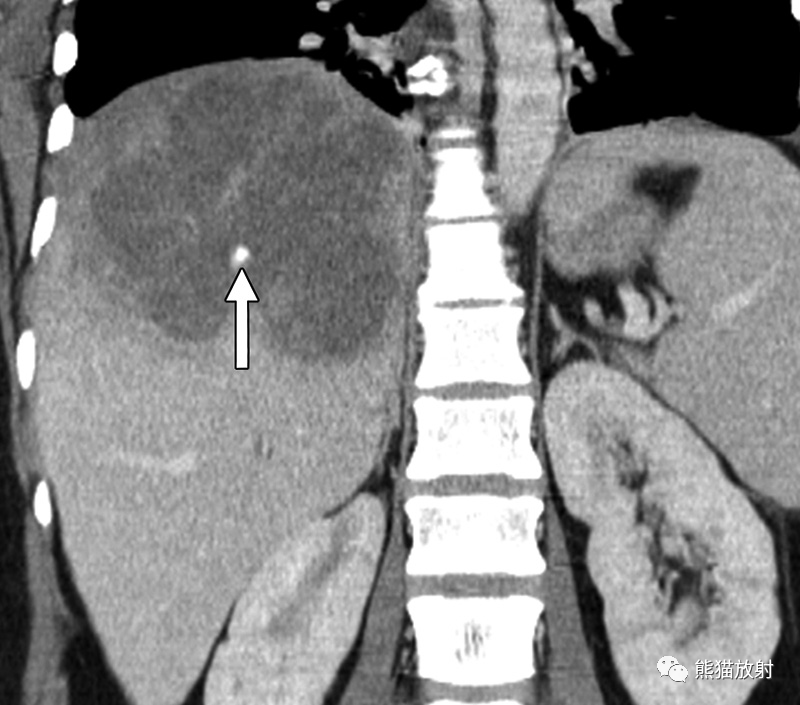

图片

57岁女性,含脂肪的肝包虫囊肿。(a)CT平扫显示肝脏病灶内有肉眼可见的脂肪球(箭)。囊内脂肪可能来源于胆汁中的脂质成分,并意味着交通性破裂。(b) T1WI同相位图像显示病灶内有高信号灶(箭)。(c) T1WI反相位图像显示囊肿内有肉眼可见的脂肪,表现为化学位移伪影和脂质成分周围信号减低(箭)。